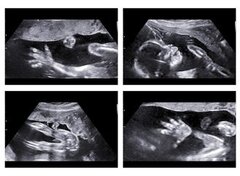

Échographie de plaisir : faut-il légiférer ?

Déjà très présent en France et au Royaume-Uni, le phénomène des échographies de plaisir se développe de plus en plus en Belgique. Une échographie dite de plaisir (ou affective) n'est pas un acte médical. “Il s'agit d'un premier contact avec le bébé”, explique la responsable de Babybelly (un centre de bien-être et d'imagerie pour femmes enceintes). Elle parle d'ailleurs plus volontiers d'“échographies souvenirs” .

Catherine Fonck, médecin et chef de groupe (CdH) à la Chambre, va interroger la ministre de la Santé, Laurette Onkelinkx, sur ce phénomène en expansion. “Il faut légiférer”, dit-elle. “Ce qui est interpellant, c'est la manière dont l'échographie est réalisée”, reprend Catherine Fonck. “Le foetus subit une exposition prolongée aux ultrasons, le plus souvent braqués sur la tête ou les organes génitaux. Or, on connaît toute la fragilité du foetus pendant la période de formation.”